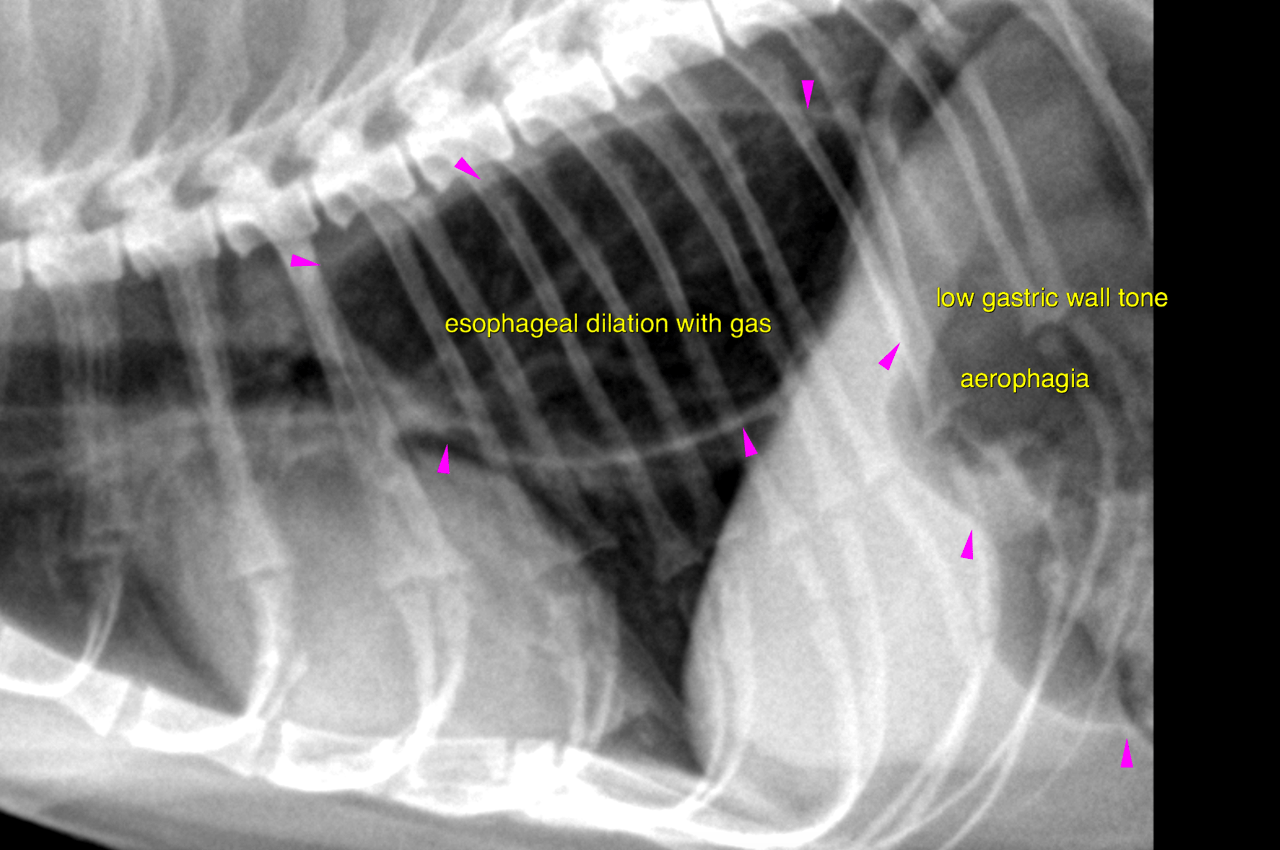

lateral and vd thorax – There is no evidence of an

abnormal pulmonary infiltrate throughout the lungs.

Moderate generalized dilation of the intrathoracic esophagus with gas is noted. The

stomach is moderately distended with gas. The gastric wall tone appears to be low.

Several incomplete contraction waves appear to pass through the gastric fundus and

body.